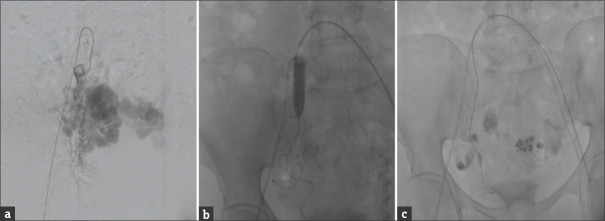

子宫动静脉畸形(UAVM)是一种罕见的发生在绝经后妇女。我们对文献的回顾显示,在这一人群中,只有少数记录在案的UAVM病例。这些患者的治疗选择包括子宫动脉栓塞(UAE)、医疗管理和子宫切除术。我们遇到了一个54岁的妇女,绝经9年,在绝经前3个月有出血史。影像学检查证实了UAVM的存在。尽管尝试了阿联酋手术,但手术失败了,因此决定进行子宫切除术,并一丝不苟地注意尽量减少失血。值得注意的是,在绝经后妇女中,子宫切除术可能并不总是能取得良好的结果,因此强调子宫切除术作为一种安全的替代治疗选择,没有任何术中过多出血。

Uterine arteriovenous malformation (UAVM) is an infrequent occurrence among postmenopausal women. Our review of the literature revealed only a few documented cases of UAVM in this demographic. Treatment options for these patients encompass uterine artery embolization (UAE), medical management, and hysterectomy. We encountered a case involving a 54-year-old woman, postmenopausal for 9 years, who presented with a history of postmenopausal bleeding over the preceding 3 months. Imaging studies confirmed the presence of UAVM. Despite an attempted UAE, the procedure proved unsuccessful, leading to the decision to perform a hysterectomy with meticulous attention to minimizing blood loss. Notably, UAE may not consistently achieve favorable outcomes in addressing UAVM in postmenopausal women, thereby underscoring the consideration of hysterectomy as a safe alternative - treatment option without any excessive intraoperative bleeding.